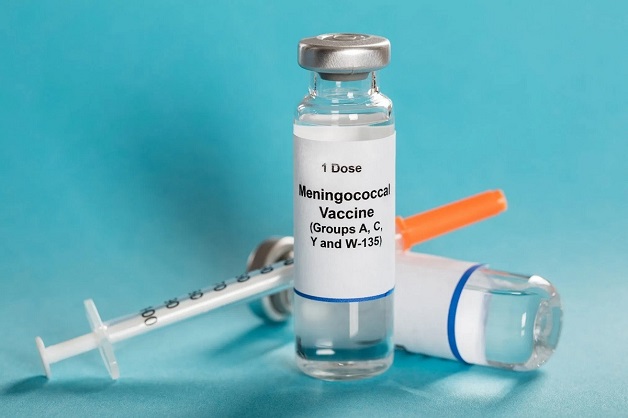

– Vắc xin viêm màng não mô cầu A, C, Y và W135: Vắc xin này phòng các bệnh bao gồm các loại vi khuẩn gây bệnh A, C, Y và W135. Vi khuẩn này thường được truyền từ người sang người thông qua tiếp xúc gần gũi hoặc hít thở các giọt bắn khi ho hoặc hắt hơi. Bạn có thể tiêm loại vắc xin này cho trẻ giai đoạn từ 9 tháng tuổi đến 55 tuổi, và tiêm 1 đến 2 mũi tùy tình huống. Với trẻ từ 9 đến 23 tháng tuổi nên tiêm đủ 2 mũi, mỗi mũi cách nhau 3 tháng. Từ 2 đến 55 tuổi tiêm 1 liều duy nhất.